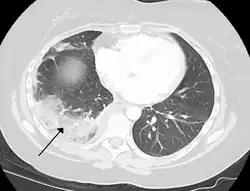

Chest CT (axial lung window)

Chest CT (coronal lung window)- Chest CT (axial lung window)